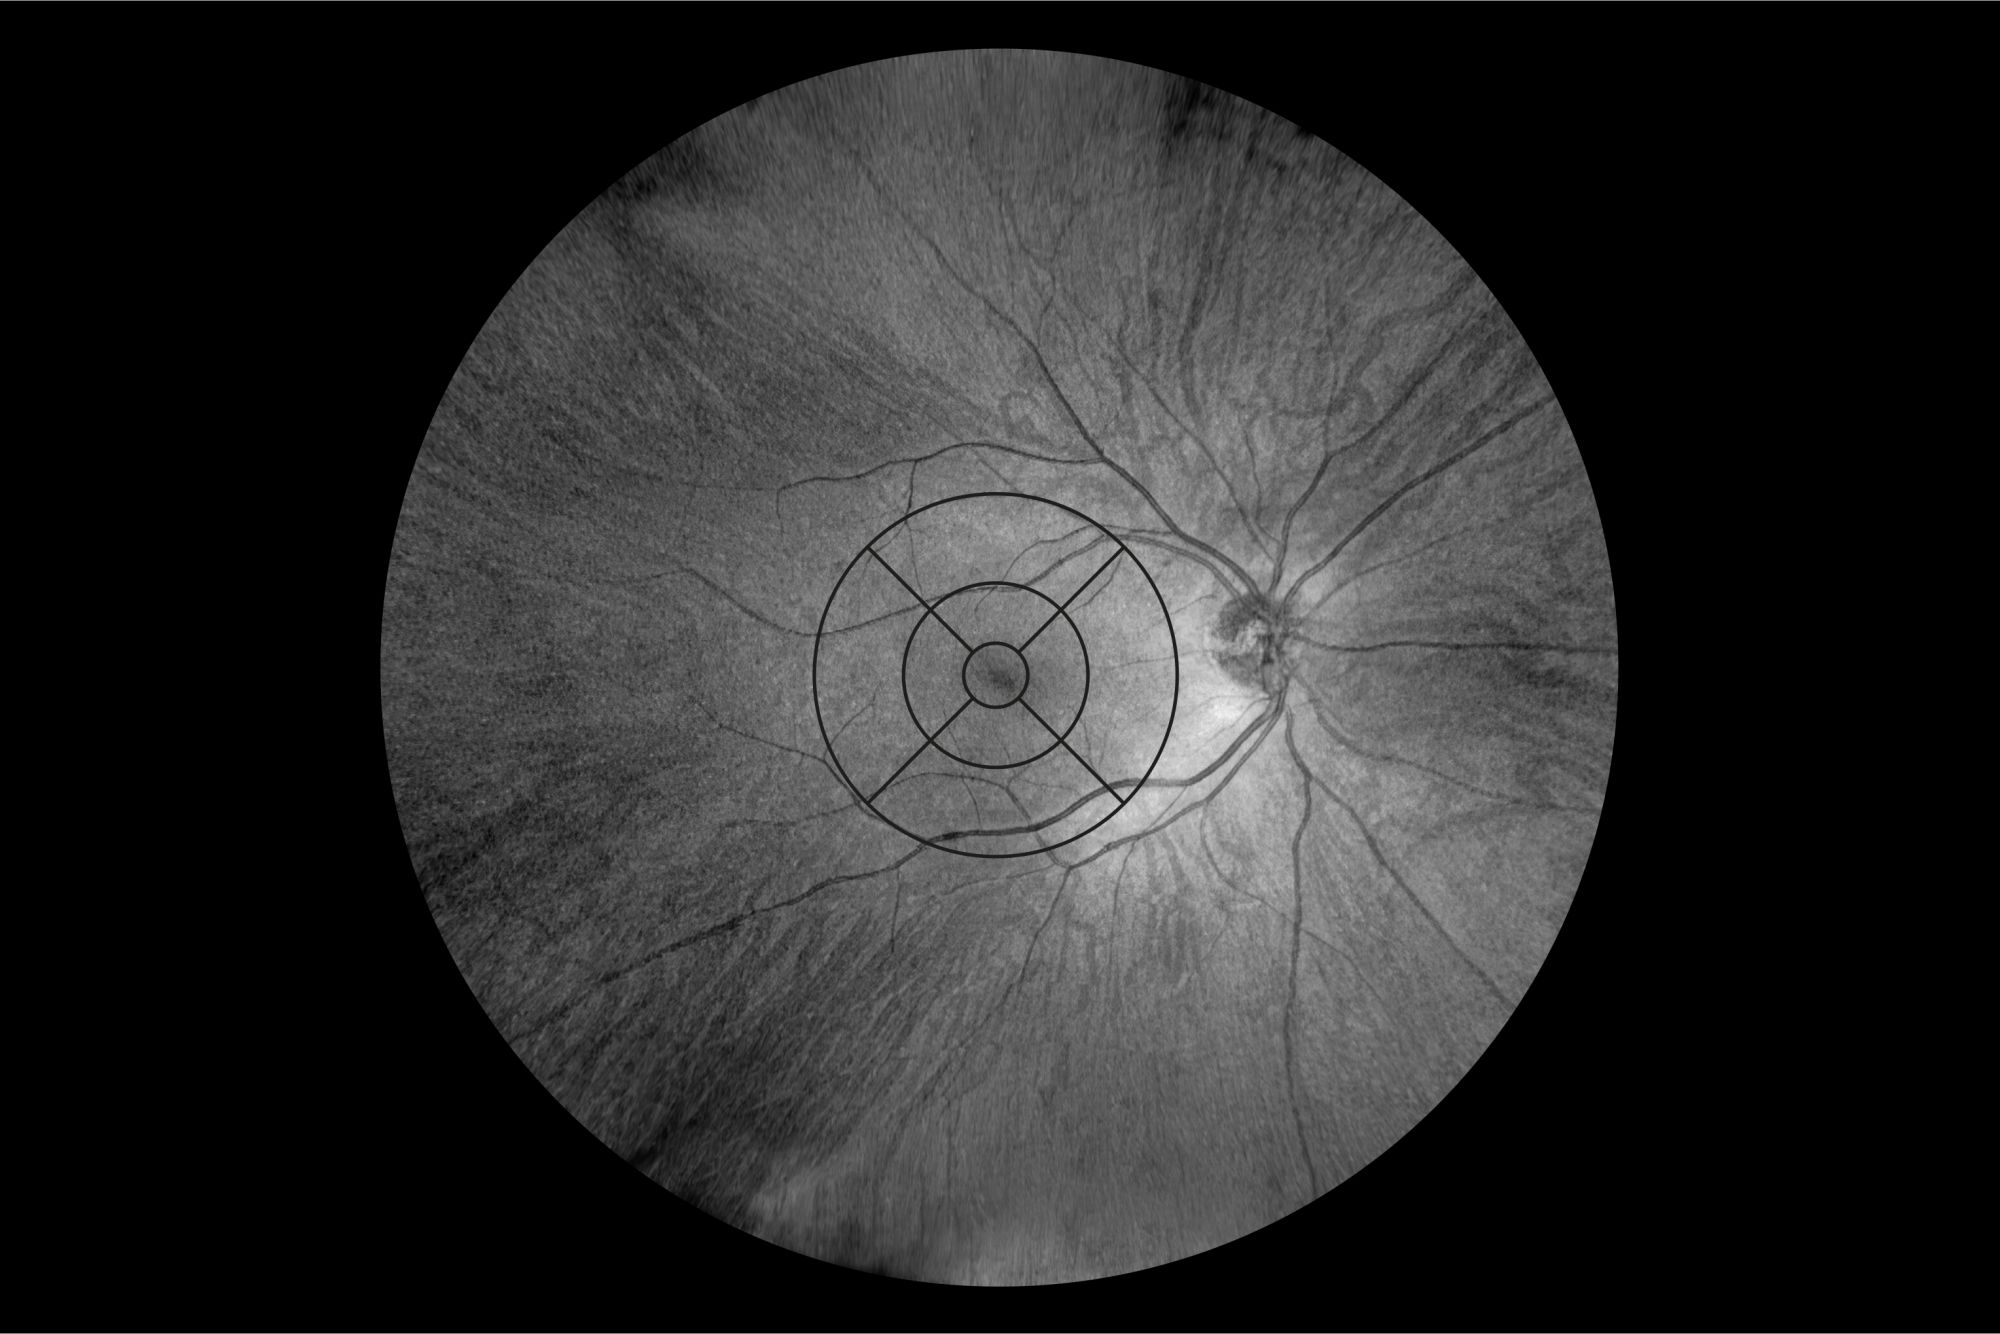

3.5. Retinal Thickness Measurements

The agreement of retinal thickness measurements between UWF and standard 10 mm Retina 3D scans in healthy individuals is shown in Table 1 and Figure 17. The mean thickness measurement difference for the ETDRS sectors is as follows: Central: −1.37 ± 2.96 µm (the 95% limits of agreement (LoA) on Bland–Altman plots ranged from −6.82 to 2.43); Inferior Inner: −2.81 ± 1.09 µm (95% LoA, −4.94 to −0.68); Inferior Outer: −1.31 ± 2.58 µm (95% LoA, −6.38 to 3.75); Nasal Inner: −1.46 ± 1.19 µm (95% LoA, −3.79 to 0.88); Nasal Outer: −0.56 ± 2.61 µm (95% LoA, −5.67 to 4.55); Superior Inner: −2.71 ± 3.16 µm (95% LoA, −8.91 to 3.48); Superior Outer: −1.82 ± 1.39 µm (95% LoA, −4.55 to 0.91); Temporal Inner: −1.77 ± 2.24 µm (95% LoA, −6.16 to 2.62); and Temporal Outer: −3.61 ± 1.43 µm (95% LoA, −6.41 to −0.81).

Figure 17. Bland–Altman plots for a thickness profile comparison between UWF and a standard retina scan (Retina 3D) in ETDRS sectors.